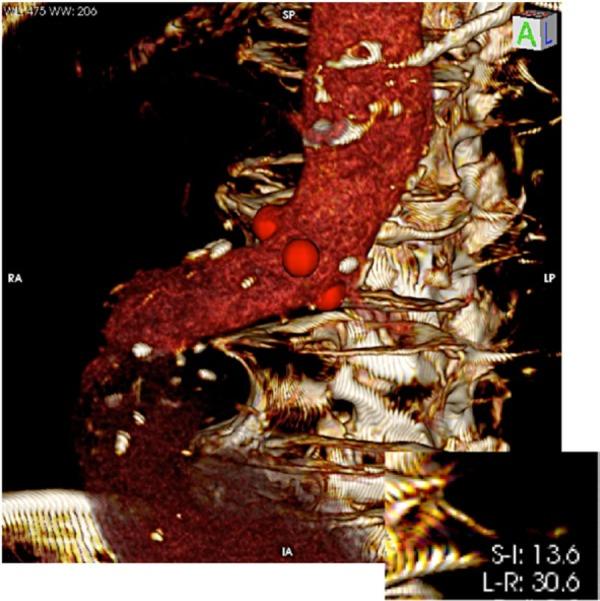

Endovascular aneurysm repair requires the precise deployment of the graft. In order to achieve accurate positioning, the anatomical and morphological characteristics of the aorta and its branches is mandatory. Software that perform three dimensional reformatting of multislice tomographic images, allow for the study of the whole aorto-iliac axis and the perpendicular visualization of the origin of the renal arteries. The correct length of the proximal neck can be evaluated and adequate graft fixation and sealing may be foreseen. A technique is presented, using an software, for the orthogonal correction of the position of the renal arteries in relation to the proximal neck, which may guide the radioscopic orientation intraoperatively.

Within a multiplanar tomographic image reconstruction, virtual triangulation allows for the three dimensional orthogonal correction of the renal arteries' ostia position. The predetermined best angulations for visualization are annotated and used for the positioning of the surgical C-arm.

RESULTS/DISCUSSION: Some authors discuss that the anatomic position of the renal vessels seen on the tomographic scan can change during the surgical procedure. It is known that the renal arterys' angular positioning does not alter, even after insertion of stiff guidewires, introducers, and the endograft itself. Therefore, it is possible, using concepts of spacial geometry and orthogonal correction, to predict the ideal bidimensional intraoperative positioning of the radioscopy device in order to reproduce the optimized renal artery ostial projection, ensuring the best accuracy during endograft deployment.